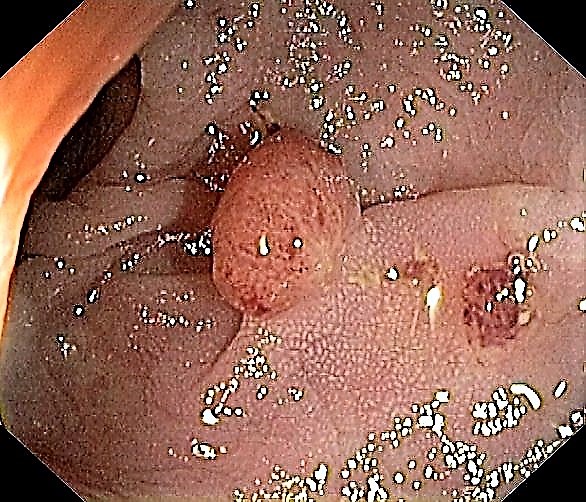

Sigmoid Tubular Adenoma with Chicken Skin Mucosa

A Small Sigmoid Tubular Adenoma with Chicken Skin Mucosa

Slight Mucosal Changes are frequently seen adjacent to a colorectal cancer or adenomas. First described by Shatz BA et al, they are called Chicken Skin Mucosa (CMS), and are supposed to occur as a result of fat accumulation in macrophages in the lamina propria adjacent to colonic neoplasms. In a series of 852 consecutive colonoscopies CMS was found adjacent to eight of 10 distal colorectal cancers, one of four of proximal colon cancers and 16 of 42 distal adenomas.